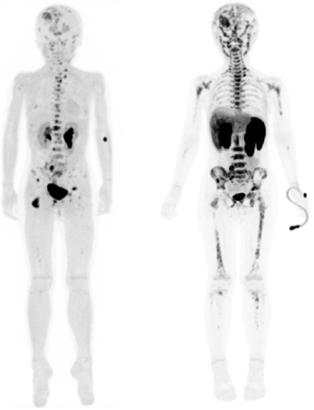

Los tejidos malignos mayormente desdiferenciados son ávidos por 2-[ 18 F]FDG debido a una mayor tasa de metabolismo de la glucosa (Figura 2). El PET con 2-[ 18 F]FDG se utiliza cada vez más en neoplasias malignas pediátricas, incluido el neuroblastoma. Varios estudios han confirmado que la mayoría de las lesiones de neuroblastoma concentran 2-[18F]FDG, el cual se acumula en el neuroblastoma no ávido de mIBG. El 2- [18F]FDG se recomienda como reempla-

Figura 2A) Estudio PET con 2[18F]-FDG, positivo para captación del radiofármaco en esqueleto axial y apendicular en un paciente con diagnóstico de Neuroblastoma de 9 años.

Figura 2B) Estudio PET/RM con 2[18F]-FDG donde se identifican las lesiones funcionales con corregistro anatómico en esqueleto axial y apendicular. Estas imágenes denotan un neuroblastoma de estirpe probablemente desdiferenciada y de pobre pronóstico.